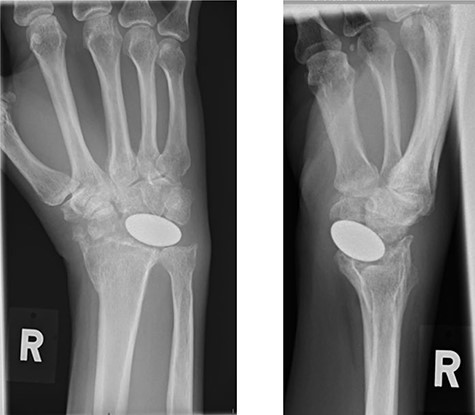

Radiographs demonstrated that the Pyrocarbon implant was palmarly displaced and rotated 90 degrees; it had migrated into the carpal tunnel/ distal forearm (Fig. 2). The clinical diagnosis was compression of the ulnar due to the migration of implant. Surgery was carried out 1 month later during which the Pyrocarbon Amandys wrist implant was removed through a volar approach (Fig. 3) and total wrist fusion was performed using a straight Arbeitsgemeinschaft für Osteosynthesefragen (AO) wrist fusion plate (Fig. 4). The surgery successfully relieved all wrist pain and was accompanied by prompt resolution of symptoms of ulnar nerve compression; she was discharged from follow-up approximately 3 months after surgery.

X-rays of the right hand showed palmar displacement of the pyrocarbon implant.